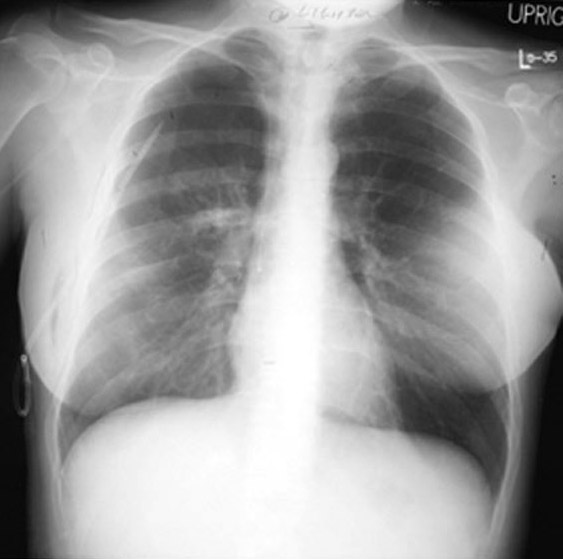

Review the chest x-rays below which show  pneumothorax and following chest tube insertion.

Chest tube in place